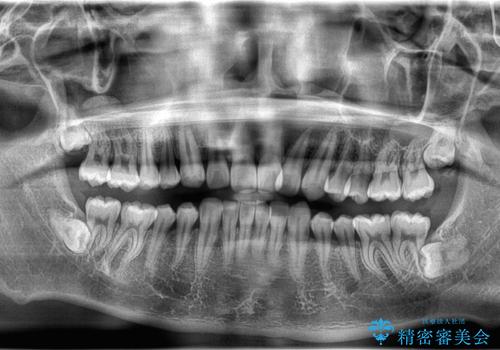

- 歯のデコボコと過蓋咬合を主訴に来院された患者様です。

アーチの拡大とIPRを行い非抜歯で治療を行いました。

歯を抜かずに叢生(デコボコ歯列)と過蓋咬合を改善する事が出来ました。

インビザラインによる治療でも十分に美しい歯並びを実現でき、患者様にも大変ご満足いただけました。